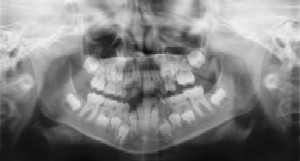

Dental Radiographs (X-Rays)

Radiographs (X-Rays) are a vital and necessary part of your child’s dental diagnostic process. Without them, certain dental conditions can be missed.

Radiographs allow dentists to diagnose and treat health conditions that cannot be detected during a clinical examination, and they detect much more than cavities. For example, radiographs may be needed to survey erupting teeth, diagnose bone diseases, evaluate the results of an injury, or plan orthodontic treatment. If dental problems are found and treated early, dental care is more comfortable for your child and more affordable for you.

The American Academy of Pediatric Dentistry recommends radiographs and examinations every six months for children with a high risk of tooth decay. On average, most pediatric dentists request radiographs approximately once a year. Approximately every 3 years, it is a good idea to obtain a complete set of radiographs, either a panoramic and bitewings or periapicals and bitewings.

Pediatric dentists are particularly careful to minimize the exposure of their patients to radiation. With contemporary safeguards, the amount of radiation received in a dental X-ray examination is extremely small. The risk is negligible. In fact, dental radiographs represent a far smaller risk than an undetected and untreated dental problem. Today’s equipment filters out unnecessary x-rays and restricts the x-ray beam to the area of interest. High-speed film and proper shielding assure that your child receives a minimal amount of radiation exposure.